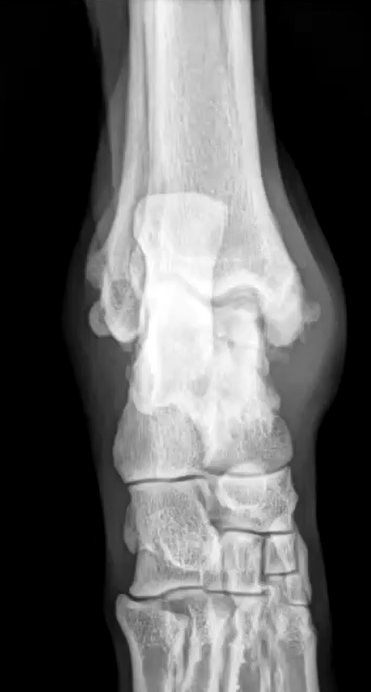

Describe osteochondrosis in the tarsus?

Most common on medial trochlear ridge

What are the radiographic findings of osteochondrosis of the tarsus?

Flattening or subchondral defect of trochlear ridge

Widening of joint space

Subchondral sclerosis

DJD

Mineralized flap

Osteochondrosis dessicans